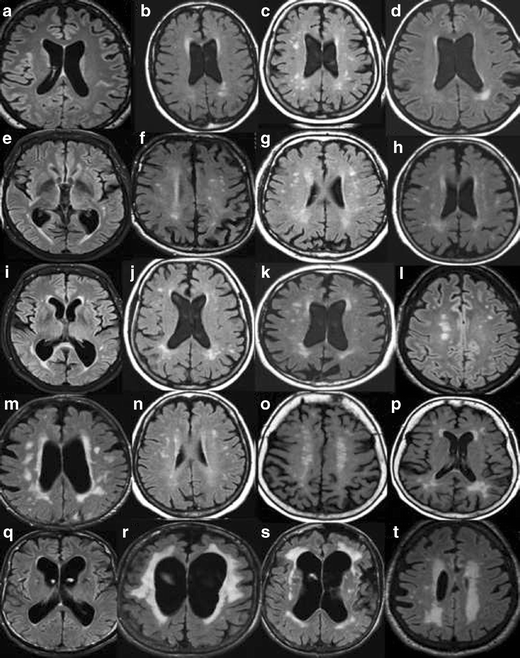

A. Rating of white matter hyperintensities (WMH) according to the Fazekas scale on MRI. Interpretation key. Numbers equal the corresponding image in the supplementary PDF file. a/2) Fazekas 0. Entire cerebrum is without punctate WMH. WMH in the pons and in the cerebellum are not included in the rating – but should be mentioned in the referral. b/19) Fazekas 1. c/14) Fazekas 1. Still punctate WMH. d/15) Fazekas 1. One single lesion < 2 cm and some punctate lesions. e/1) Fazekas 1. Small punctate WMH grouped but separated along the left posterior horn of the lateral ventricle. f/3) Fazekas 1. Grouped but not linked WMH. g/9) Fazekas 1. Many separate WMH. h/12) Fazekas 1. i/18) Fazekas 1. All WMH are seen as separate dots. No connecting bridges. j/17) Fazekas 2, Connecting bridges. k/20) Fazekas 2. Connecting bridges close to the right posterior horn. l/4) Fazekas 2. WMH are linked, but can still be seen as separate lesions. m/7) Fazekas 2. The WMH are beginning to confluate. Individual WMH are still seen. n/13) Fazekas 2. Connecting bridges between lesions. o/10) Fazekas 2. Borderline to Fazekas 3 with bridging between WMH still visible, starting to confluate. p/11) Fazekas 2–3. q/8) Fazekas 3. Borderline Fazekas 2, but the WMH on the left side measures more than 2 cm and grouped WMH are confluent to some extent. r/5) Fazekas 3. s/6) Fazekas 3. Confluent lesions around the frontal horns and confluent thin lesions in the right external capsule, and not so pronounced in the same area on the left side. t/16) Fazekas 3 .B. Rating of white matter hyperintensities (WMH) according to the Fazekas scale on CT. Interpretation key. Numbers equal the corresponding image in the supplementary PDF file. a/2)Fazekas 0–1. No lesions are seen, however punctate lesion may exist. b/7) Fazekas 1. Punctate lesions frontal bilaterally, more obvious right frontal. c/11) Fazekas 1. Lesion in the external capsule bilaterally. d/17) Fazekas 1.Single lesion frontal left. e/15) Fazekas 1. Just small caps around the frontal horns and 2 smaller diffuse punctate lesions in the frontal lobe on the right side. f/20) Fazekas 2. Lesions in the external capsules with connecting bridges. g/3) Fazekas 2. Small lesions close to frontal and posterior horns and small lesions in the external capsules.h/4) Fazekas 2. Small lesions in the external capsule, bilaterally. i/13) Fazekas 2. j/18) Fazekas 2. Lesions in the external capsules. k/12)Fazekas 2–3 depending on the size of the lesions surrounding posterior horns. l/1)Fazekas 3. Confluating lesions around the frontal and posterior horns and in both external capsules.m/5) Fazekas 3.n/6) Fazekas 3. o/8)Fazekas 3. p/9) Fazekas 3. q/10) Fazekas 3. r/14) Fazekas 3. s/19) Fazekas 3. t/16) Fazekas 3